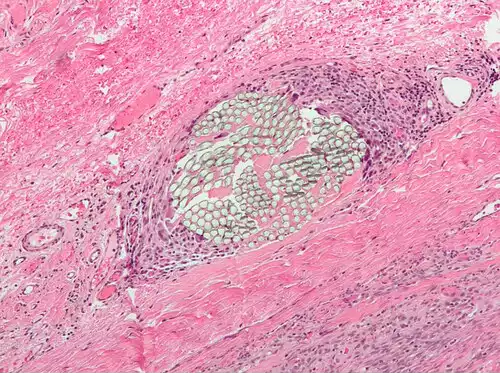

غول یاخته ( به انگلیسی: Giant Cell ) توده ای است که از یگانگی چند یاخته متمایز تشکیل شده باشد. این توده که بیشتر درشت خوارها آن را تشکیل می دهند، می تواند در پاسخ به یک عفونت مانند سل، ایدز، تبخال یا یک پیکره بیرونی باشد.

غول یاخته هایی که چندهسته ای هستند ( اختصاری  MGC ) از چسبیدن خطی مونوسیت ها و درشت خوارها ( ماکروفاژها ) حاصل می گردند.

نورویش بدخیم یاخته های پوششی را که از غول یاخته ها تشکیل شده است، پوش چنگار غول یاخته ای ( giant cell carcinoma ) می گویند.